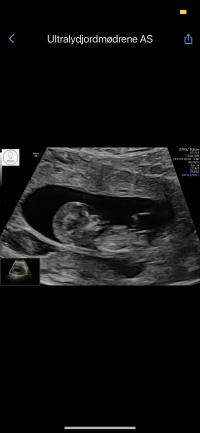

Ååh så kjekt! Lite som er bedre enn det!Så er uke 8+0, ble satt en uke frem Vis vedlegget 439187